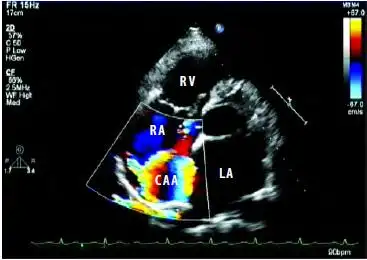

彩色多普勒超声诊断右冠状动脉右房瘘合并右房内冠状动脉瘤1例